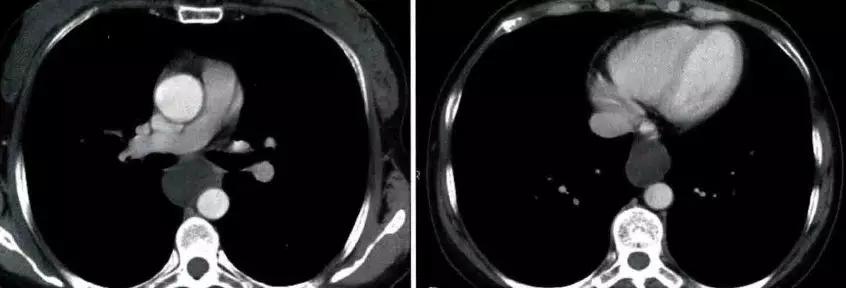

非侵袭性胸腺瘤CT图像

a. CT平扫示前上纵膈主动脉弓与胸骨间软组织密度肿块,密度均匀,边缘浅分叶状 b. CT增强示肿块均匀强化,肿块与主动脉弓之间脂肪间隙清晰

侵袭性胸腺瘤CT图像

a. CT平扫示肺动脉与胸骨间肿块,密度尚均匀,形态不规则b. CT增强示肿块不均匀强化,见低密度囊变区域,肿块与肺动脉之间脂肪间隙消失,肺动脉壁模糊。